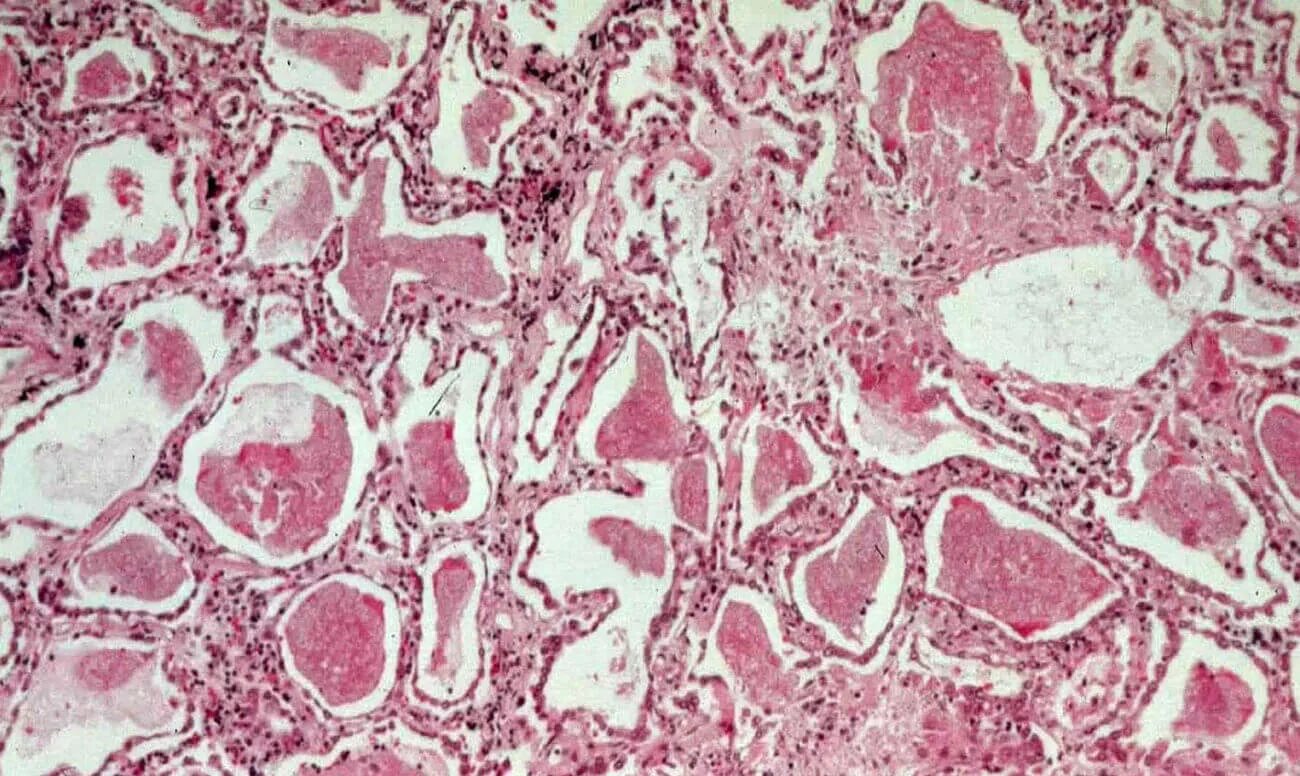

Серозный выпот